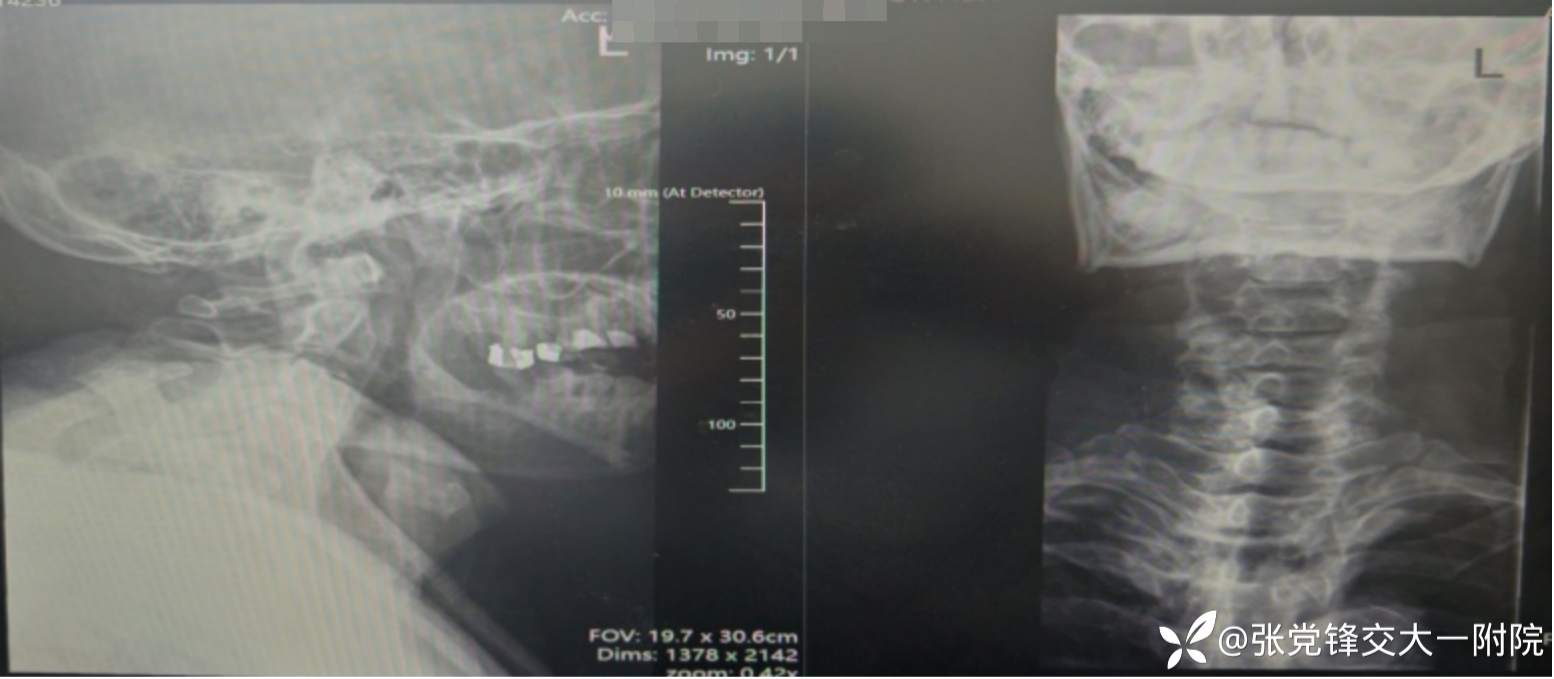

【影像学检查】

术前CT

术前x线片

全身骨显像:胸2-3椎体骨代谢增高,结合病史考虑脊柱结核可能。

1.胸椎结核并不全瘫;2.胸椎管狭窄并脊髓损伤;3.高血压;4.2型糖尿病